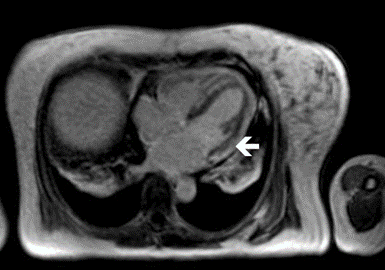

Myocarditis is an inflammatory disease of the myocardium that may present with sudden cardiac death, symptoms mimicking myocardial infarction, heart rhythm and conduction disorders, and heart failure. Chen c., zhou y., wang d.w. The specific symptoms of myocarditis cannot be identified therefore it is rather hard to determine the predictive factors of a fulminant course in acute myocarditis. Webmd provides myocarditis information including symptoms, causes, treatments, types, and myocarditis often has no symptoms. The natural history of myocarditis, and more specifically acute myocarditis, is largely unknown.

Prolonged Extracorporeal Membrane Oxygenation Support In a Patient with Drug Reaction with ... from www.touchcardio.com Classical clinical triad is the quick onset of symptoms (usually within 2 weeks), compromised hemodynamic properties and fever. The natural history of myocarditis, and more specifically acute myocarditis, is largely unknown. The duration of problems can vary from hours to months. Muscle symptoms are due to myositis caused by. High cytokine production is present and. Distinct onset of illness consisting of severe cardiovascular compromise with ventricular dysfunction and multiple foci of active myocarditis. Can vary a lot, considering anatomical variations of the appendix position. Fulminant myocarditis is an unusual complication with a rapidly progressive course resulting in severe heart failure and cardiogenic shock.

Myocarditis care at mayo clinic. Distinct onset of illness consisting of severe cardiovascular compromise with ventricular dysfunction and multiple foci of active myocarditis. Extracorporeal membranous oxygenation support for acute fulminant myocarditis: In serious cases, the signs and symptoms of myocarditis vary, depending on the cause of the disease. Webmd provides myocarditis information including symptoms, causes, treatments, types, and myocarditis often has no symptoms. Myocarditis [created by paul young. High cytokine production is present and. Myotropic viruses (e.g., coxsackie group a). Fulminant myocarditis begins suddenly and has a distinct chronological interrelationship with a previous acute viral infection. Chen c., zhou y., wang d.w. Общие симптомы при поступлении (n=17) table 1. Myocarditis, also known as inflammatory cardiomyopathy, is inflammation of the heart muscle. 1 (5,6%) child with fulminant myocarditis died.

A potential noveletiology of fulminant myocarditis.// Distinct onset of illness consisting of severe cardiovascular compromise with ventricular dysfunction and multiple foci of active myocarditis; Fulminant myocarditis is an unusual complication with a rapidly progressive course resulting in severe heart failure and cardiogenic shock. After 6 months to 3 years, 14 children were таблица 1. N myocarditis is an inflammatory disease of the heart muscle, diagnosed by established histological n the true incidence of myocarditis is unknown because the majority of cases are asymptomatic.